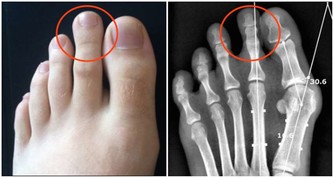

1.面部浮腫

面部浮腫,是臨床上最為典型的腎臟疾病的表現。尤其是尿毒症患者,大多數尿毒症患者在早期都會出現不同程度的浮腫的症狀。

這主要是由於人體腎臟功能受損,導致腎臟的代謝功能異常,從而使得人體的水液循環受阻,使得大量水分聚集在人體內所致。

所以,若男性經常出現面部浮腫的症狀,那就需要擔心一下自己腎臟的健康狀況,建議儘早去醫院,做個腎臟方面的檢查。